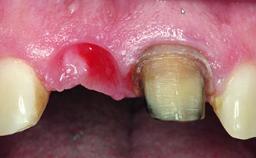

A 32-year-old female Caucasian patient with a compromised maxillary right central incisor was referred to us by a general dentist. Her chief complaints were discomfort and mobility of tooth 11 with unsatisfactory esthetics due to discoloration. The patient reported a previous trauma, some years earlier, as the origin of pathology on the afflicted tooth. Anamnesis was negative for any other dental or periodontal pathology in the remaining dentition. The patient did not take any medication and reported to be a light smoker (5–10 cigs/day). She had high esthetic expectations of her treatment. The extraoral examination revealed a high smile line with full exposure of her maxillary teeth and surrounding soft tissue in the area between the second premolars.

Bone Volume Deficient horizontally, requiring prior grafting